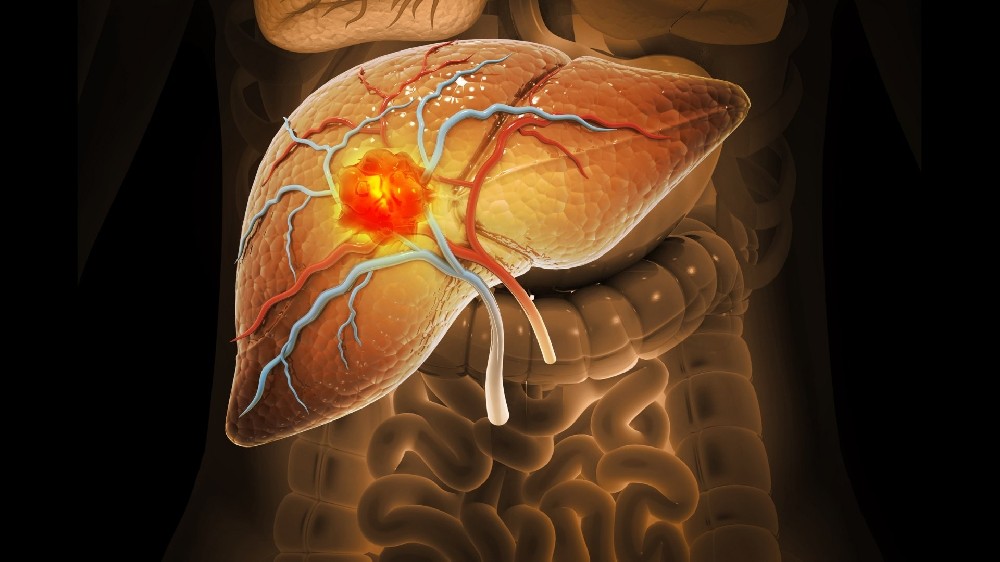

美國代謝腫瘤研究所(AICM)由李國華博士創立的世界級醫療機構,以諾貝爾獎得主Otto Warburg的 "癌細胞能量代謝學說" 爲基石,首創顛覆性 "四位一體靶向代謝療法":通過代謝重編程斬斷腫瘤能量鏈+ 節拍控瘤封鎖轉移路徑 + 基因靶向清除突變根源 + 免疫調節構築終身防禦,徹底改寫癌症治療規則!該療法已登陸美國希望之城、MD安德森癌症中心、凱特琳癌症中心等全球頂級機構,並依託香港代謝腫瘤中心及前海泰康醫院建立亞洲核心基地,專爲中晚期/難治性癌症患者提供趨近零副作用的創新性治療,實現癌痛癌疲乏突破性緩解及生存週期的治癒級延長,讓複雜病例重獲生命掌控權!